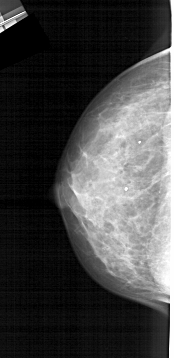

A_1272_1.LEFT_CC

LEFT_CC LINES 5011 PIXELS_PER_LINE 2431 BITS_PER_PIXEL 12 RESOLUTION 43.5 NON_OVERLAY